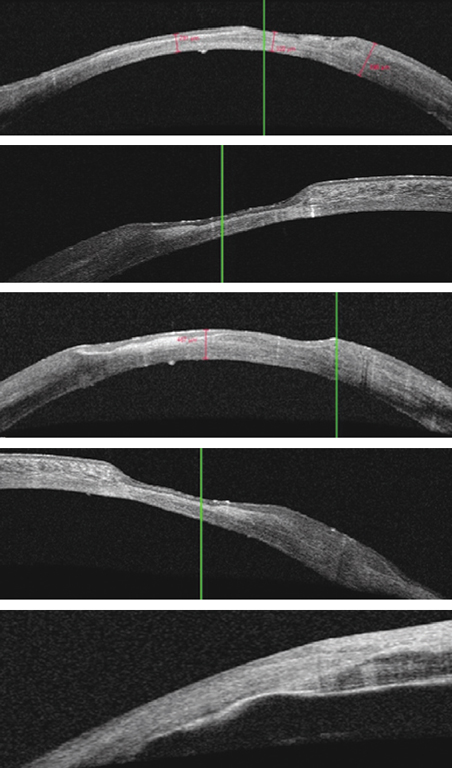

Тонометрия у пациентов с повреждениями роговицы сопряжена с некоторыми особенностями, влияющими на точность и достоверность полученных данных. Индивидуальные различия в этиологии, локализации, площади, продолжительности развития рубцовой ткани и дефектов роговицы влияли на диапазон полученных результатов в серии измерений ВГД различными методами (рис. 3, 4).

Рис. 3. Варианты изменения конфигурации поверхности роговицы

Fig. 3. Variants for changing the configuration of the corneal surface

Рис. 4. Деформация роговицы после сквозной кератопластики